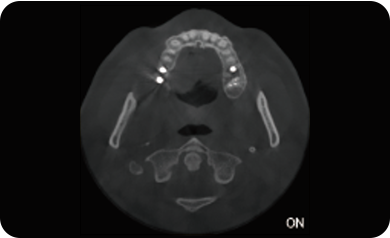

超能去伪 至臻影像

临床样片